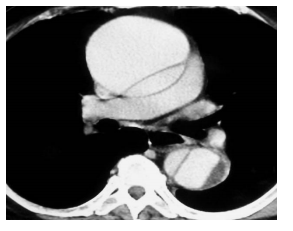

Mulher, 58 anos, apresenta dor em queimação em epigástrio associada a sudorese e vômitos. De base hipertensa e dislipidêmica, está em uso de atenolol 100 mg e losartan 50 mg para tratamento de hipertensão arterial. Admitida no pronto-socorro de clínica médica, apresentava-se sonolenta e taquipnéica, com PA 70/40 mmhg, P 28bpm, FR 28 irpm e SAT 85% em ar ambiente e com ausculta pulmonar limpa.

Realizado ECG cujo resultado se encontra abaixo.

A conduta, nesse momento, será o uso endovenoso de